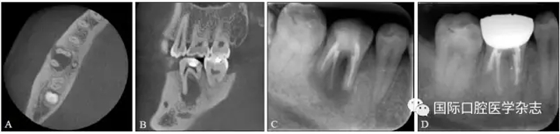

典型病例2 46牙頰側(cè)竇道經(jīng)久未愈,行根尖外科手術(shù)后竇道愈合(圖2)。

A、B:術(shù)前CBCT圖像;C:術(shù)前X線充填片;D:術(shù)后1年復(fù)查X線片,病變愈合。

圖 2 46牙根尖周炎經(jīng)顯微根尖外科手術(shù)后愈合

Fig 2 The healing of the tooth46 with periapical periodontitis after endodontic microsurgery